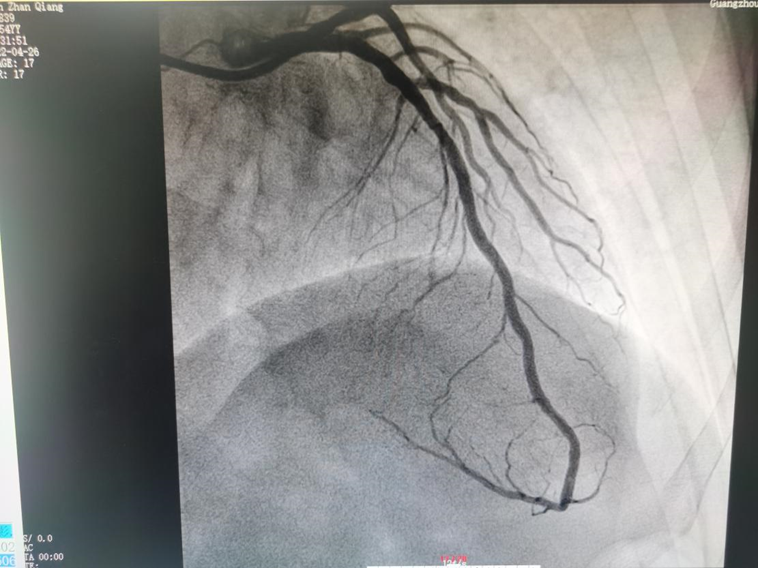

随后,广医五院心脏中心手术团队根据OCT测得的血管直径,顺利实施精确的药物球囊处理后,造影显示冠脉无夹层、穿孔,远段血流TIMI 3级,近中段病变狭窄程度低于10%。术后林叔的心肌缺血症状完全消失,未再出现胸闷痛不适,后续只需遵循医嘱用药,密切随访即可。

▲ 患者前降支造影(术后)